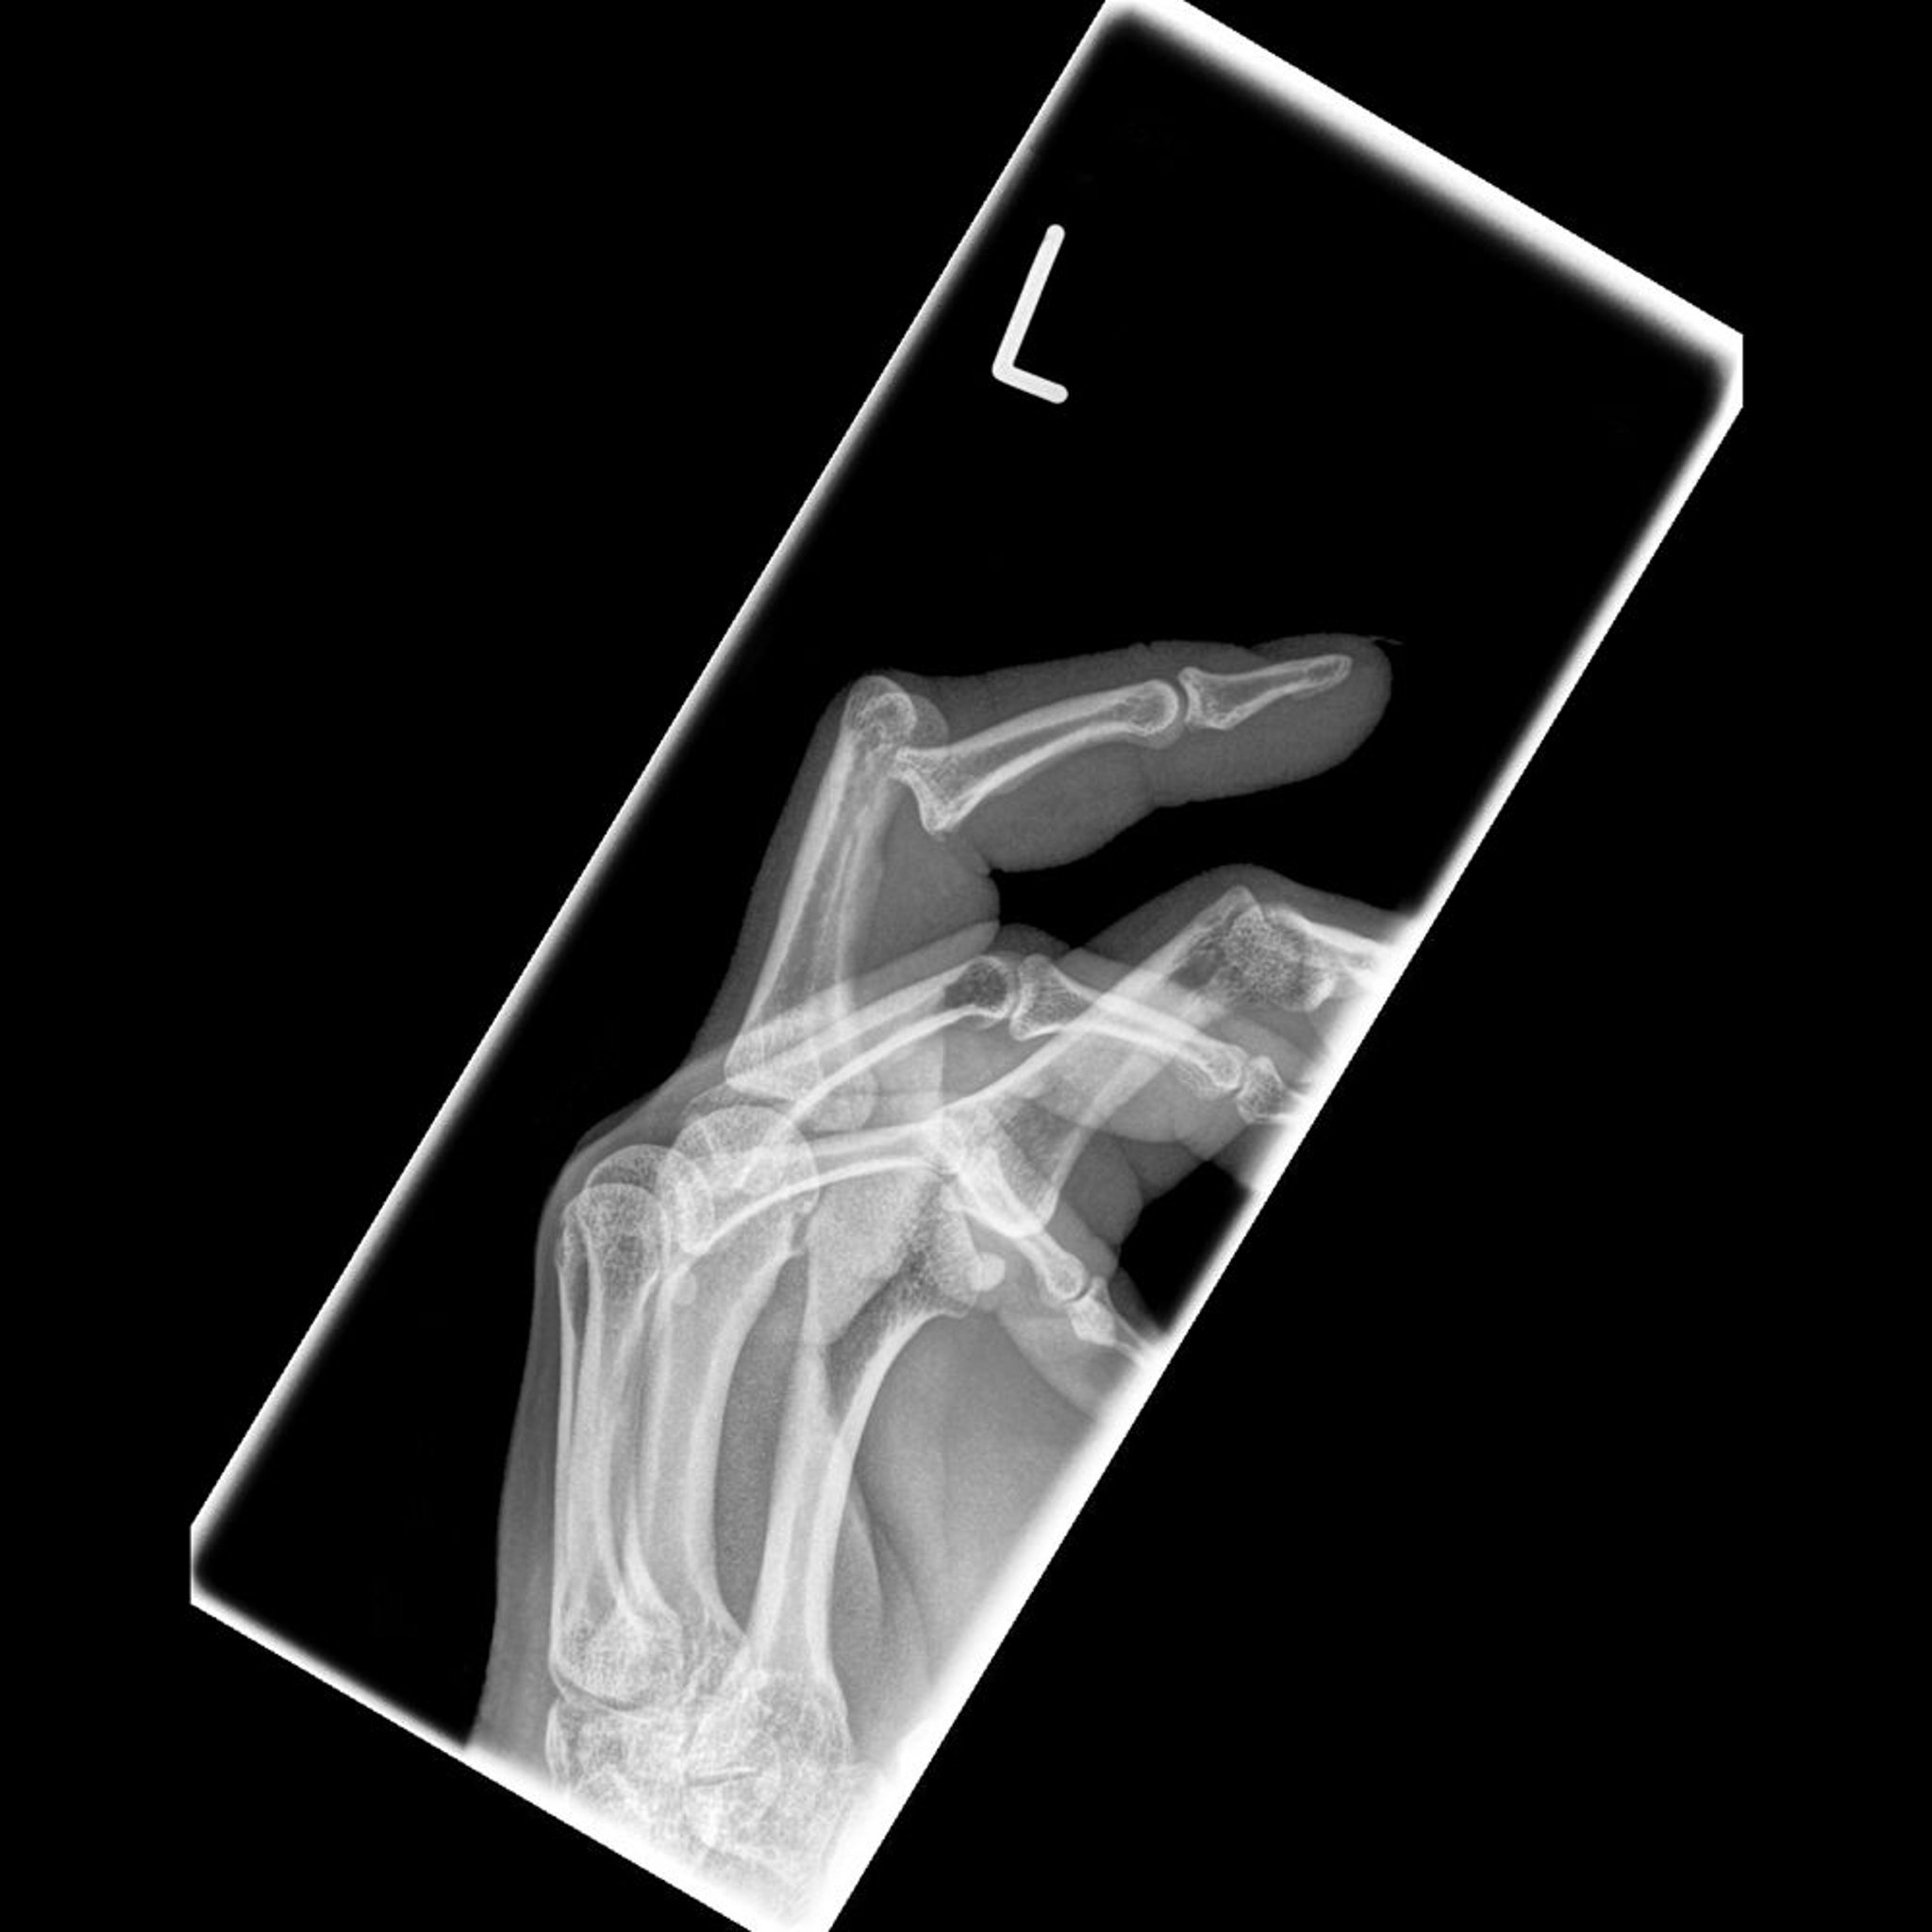

Luxación de la cara volar (palmar) de los dedos

La falange media está luxada en la cara palmar de la falange proximal.